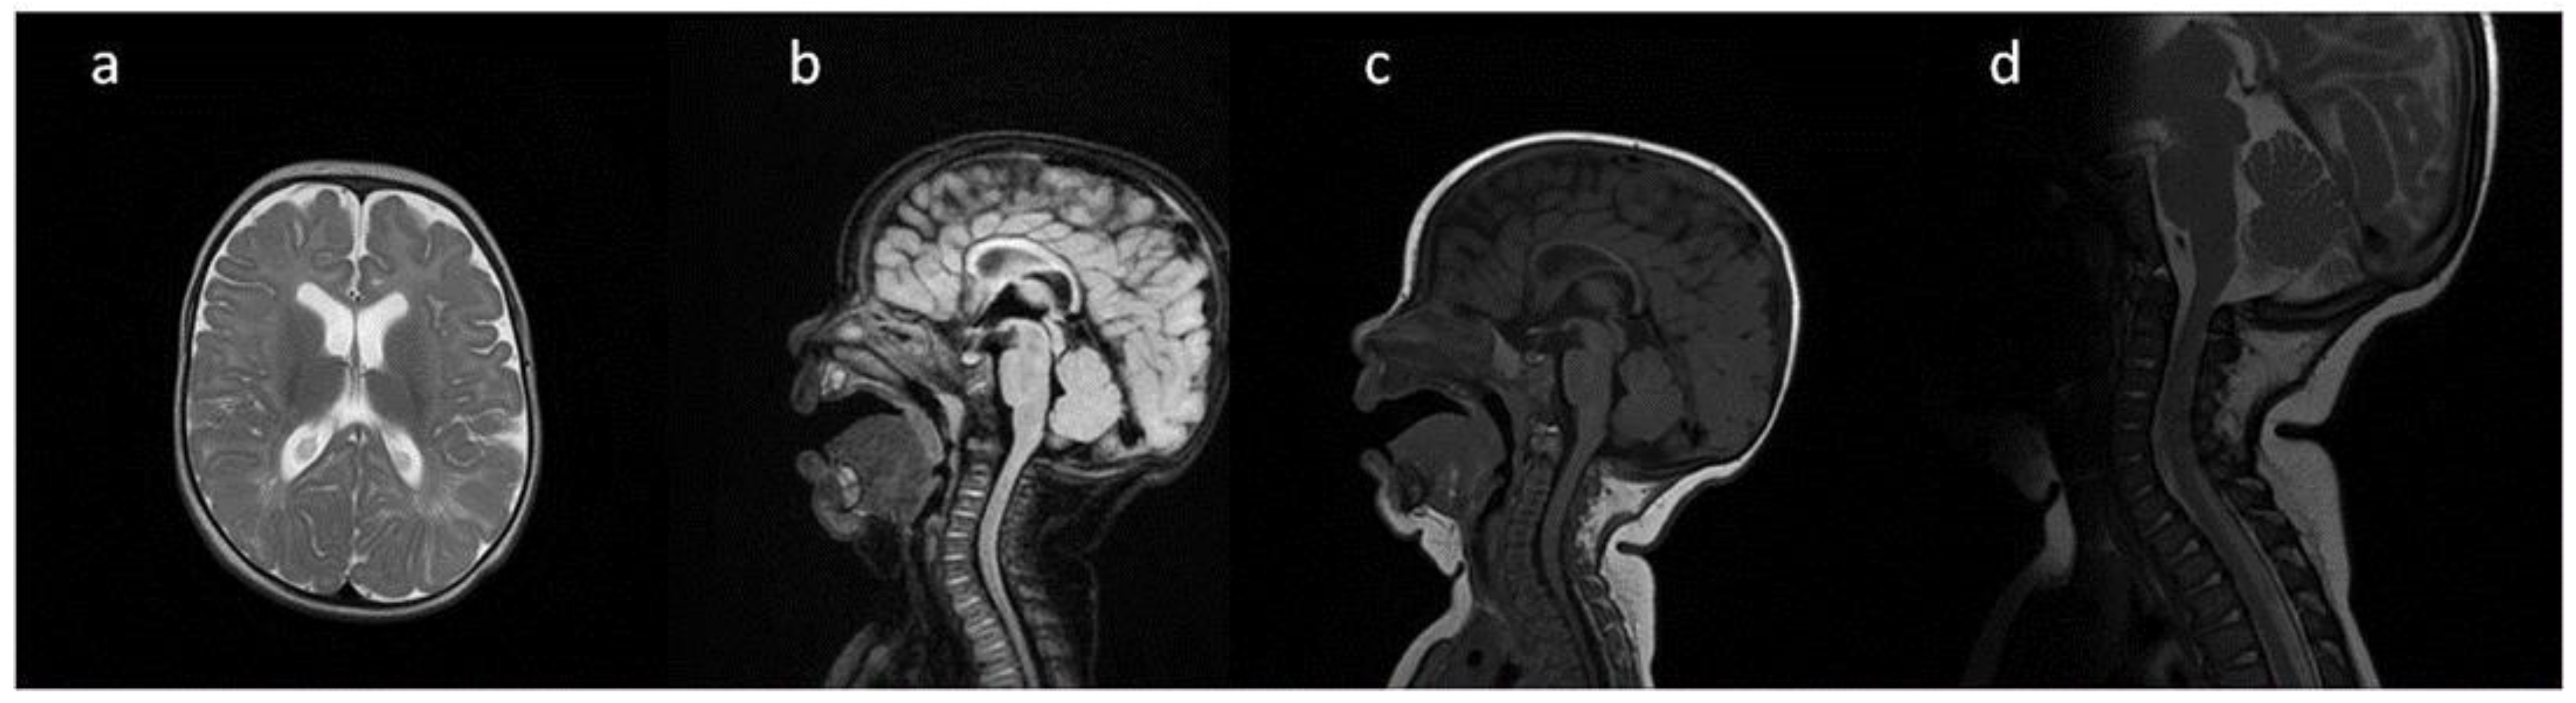

| Patient No | 1 | 2 | 3 | 4 | 5 | |

|---|---|---|---|---|---|---|

| age at exam | 4 mo | 3 yo | 1 y 2 mo | 1 y 11 mo | 3 y 2 mo | 14 yo |

| radiological imaging | ||||||

| WM signal abnormalities | + | + | + | |||

| areas of delayed myelination | + | + | + | + | + | |

| enlarged perivascular spaces | + | + | + | + | ||

| narrow corpus callosum | + | +/− | + | + | ||

| prominent ventricular system | +/− | + | +/− | + | + | |

| arachnoid cyst | + | + | ||||

| optic nerve sheath enlargement | + | + | ||||

| J-shaped sella turcica | + | + | + | +/− | + | +/− |

| craniocervical junction distortion | + | +/− | + | + | ||

| posterior fossa horns | + | + | + | + | ||

| fluid effusion temporal bone | + | + | + | + | +/− | |

| closed sagittal suture | + | + | + | |||

| vertebral bodies deformity | + | + | ||||

| intervertebral disc anomalies | + | + | ||||